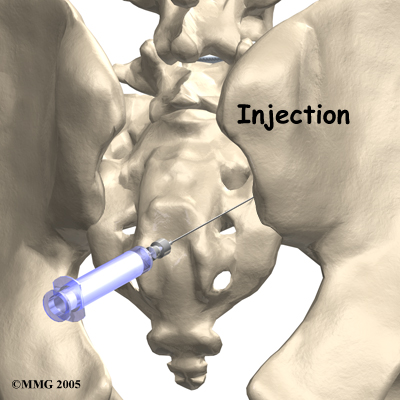

The most accurate way of determining whether the SI joint is causing pain is to perform a diagnostic injection of the joint. Because the joint is so deep, this must be done using X-ray guidance with a fluoroscope (a type of realtime X-ray). Once the doctor places a needle in the joint, an anesthetic is injected into the joint to numb the joint. If your pain goes away while the anesthetic is in the joint, then your doctor can be reasonably sure that the pain you are experiencing is coming from the SI joint.

Injections

If conservative treatment is unsuccessful, injections may be suggested by your doctor. As described above, injections are used primarily to confirm that the pain is coming from the SI joint. A series of cortisone injections may be recommended to try to reduce the inflammation in and around the SI joint. Cortisone is a powerful anti-inflammatory medication that is commonly used to control pain from arthritis and inflammation. Other medications have been injected into the joint as well. A chemical called hyaluronic acid has been used for years to treat osteoarthritis of the knee. This chemical is thought to reduce pain due to its lubricating qualities and the fact that it nourishes the articular cartilage in the synovial joints. The true mechanism of action remains unknown, but it has been used with some success in the SI joint. All of these injections are temporary and are expected to last several months at the most.